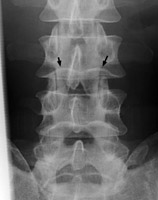

Frontal and lateral radiograph of the lumbar spine with curvature of the inferior endplate of the 4th and 5th lumbar vertebrae, which mimics the curvature of Cupid's bow aimed cephalad. The unusual, non-flat surface of the inferior endplate is a normal variant, and need not be misinterpreted as inherent osseous abnormality or adjacent pathological process.

- Click on the image for a larger versionA - Click on the image for a larger versionB